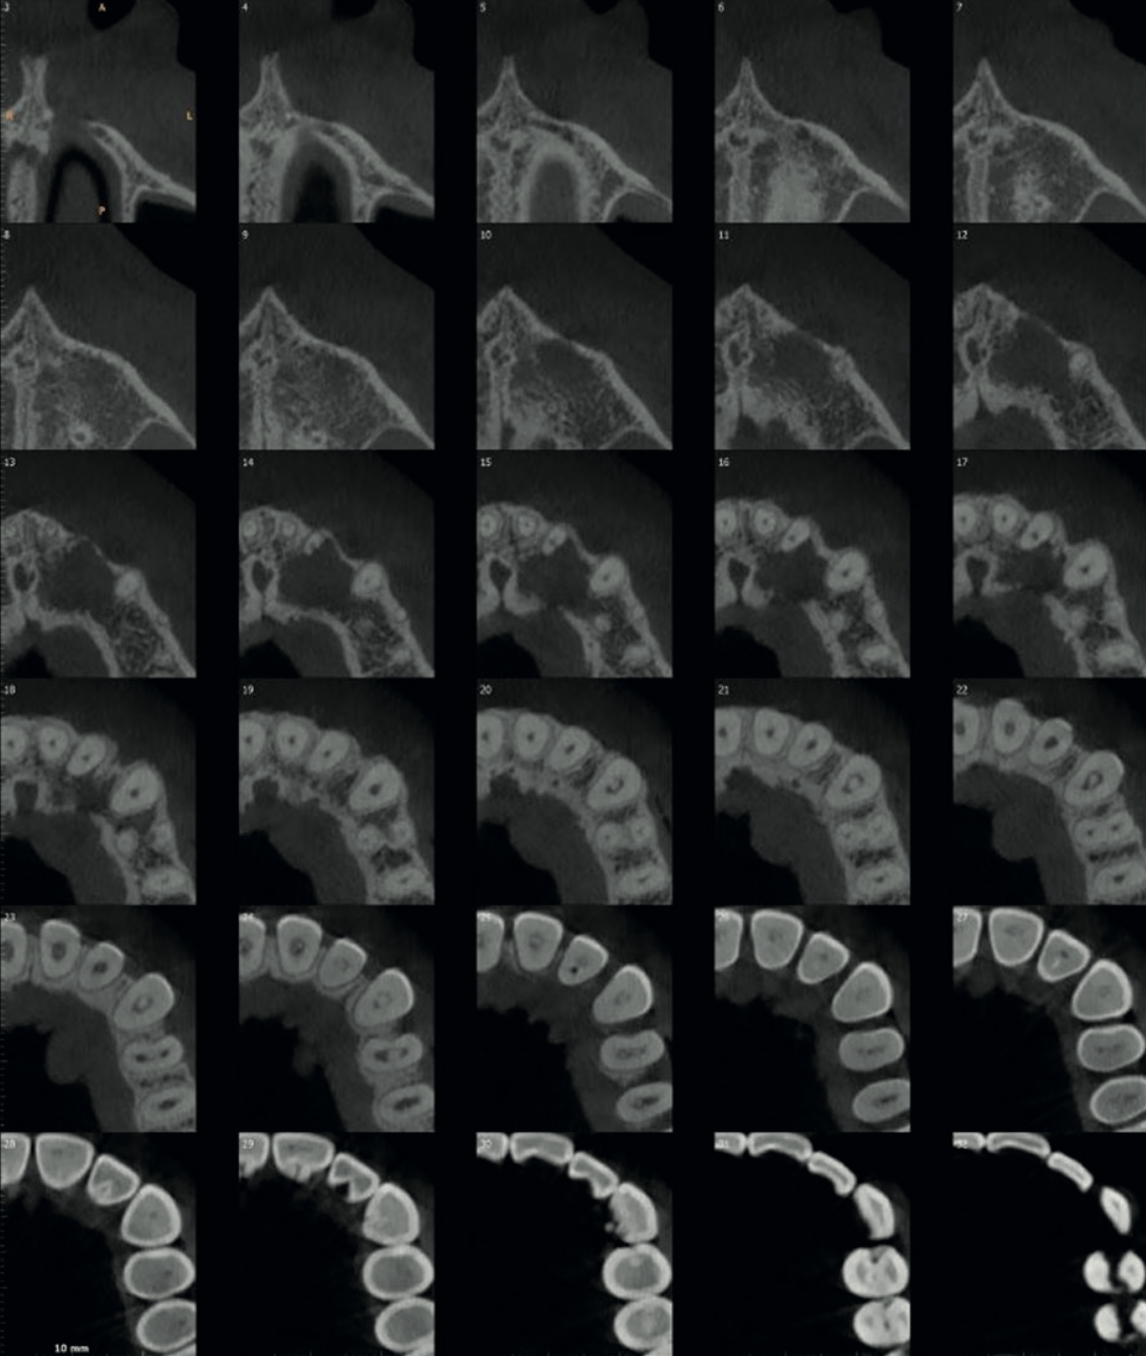

The CBCT also revealed a well-defined periapical lesion measuring 1.3 cm × 1.0 cm × 1.3 cm in the UL2–UL3 region. There was mild expansion and thinning of the cortical bone, with significant focal erosion of the palatal bone adjacent to UL3 and contiguous soft tissue thickening — explaining the palatal swelling that had prompted the referral in the first place.

Axial CBCT images showing the full extent of the periapical lesion in the UL2-UL3 region

Fig. 5 Axial CBCT slices showing the extent of the periapical lesion with cortical bone thinning and palatal bone erosion.

Coronal CBCT views showing the periapical lesion extent 3D volume-rendered view of the affected anterior maxilla

Fig. 6 & 7 Left: coronal CBCT slices delineating the lesion boundaries. Right: 3D volume-rendered image showing the bone loss from the buccal aspect.